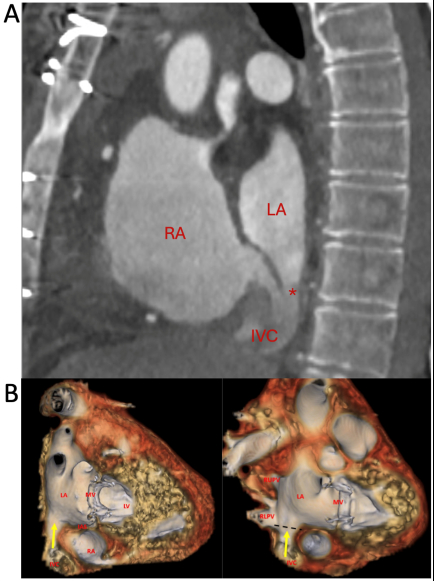

A 67-year-old woman with history of remote surgical atrial septal defect (ASD) repair in childhood and severe mitral regurgitation presented for surgical mitral valve (MV) repair. Pre-operative transesophageal echocardiography (TEE) revealed flail P2 scallop of the MV and no evidence of intracardiac shunt. She underwent redo sternotomy with chordal-sparing bioprosthetic MV replacement on cardiopulmonary bypass (CPB) via femoral cannulation. After coming off CPB, she experienced hypoxemia despite supplemental oxygen. Chest X-ray revealed no acute pulmonary pathology. Initial transthoracic echocardiogram (TTE) showed normal biventricular function, well-seated and normal position and function of the mitral bioprosthesis. TEE showed no evidence of transseptal shunting but revealed a communication between the inferior vena cava (IVC) and left atrium (LA) with continuous right to left shunting (Fig 1). CT angiography of the chest demonstrated an inferoposterior interatrial communication associated with an overriding IVC, consistent with an inferior sinus venosus defect (ISVD) (Fig 2a).

Review of historical records from her childhood surgery revealed that she was born with an interatrial communication and anomalous right pulmonary venous drainage into the right atrium – likely ISVD – that was repaired with primary suture closure of the defect that also re-routed the pulmonary venous drainage into the LA. Based on this history and CT findings, trauma from the IVC cannula likely caused reopening of the ISVD at the suture site, creating a right-to-left shunt at the precise location of the IVC override into the LA (Fig 2b).